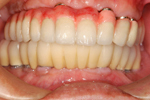

症例 4

術前

術後

術中

骨を作っている途中

40才代 男性

総額:99万円(税別)

治療期間:6ヵ月

リスク副作用:上顎洞の炎症。インプラント体の迷入。セラミッククラウンの破損。